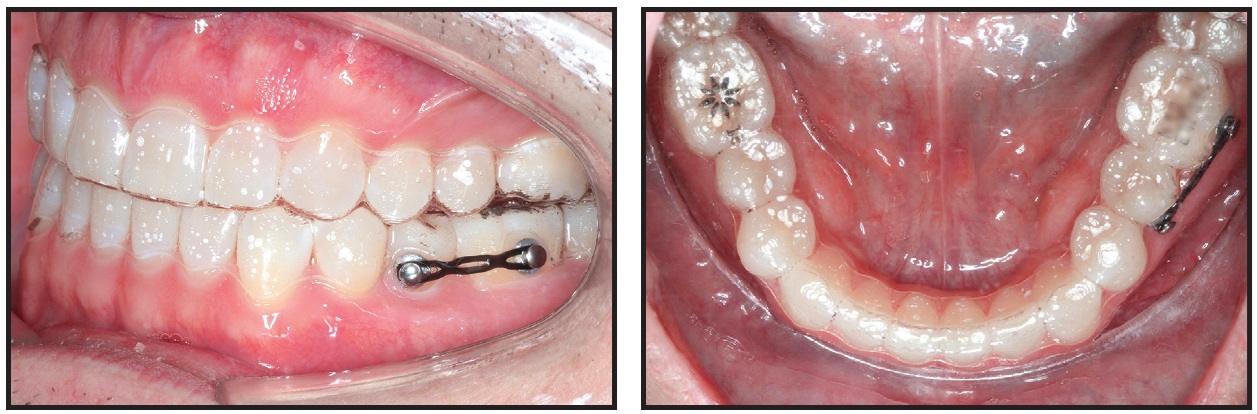

Buttons with segmental elastic chains can be effective in correcting severely rotated teeth, such as premolars (Fig. 11).2 In virtual treatment planning for such cases, it is important to compensate for undesirable side effects created by the segmental elastic chain on the anchorage teeth.

Fig. 11 Bonded buttons used with segmental elastic chain for derotation of lower left second premolar. Horizontal attachments can be placed on lingual surface of rotated premolar and mesiobuccal surface of first molar; consider compensating for elastic chain by programming slight mesial-out rotation of lower first molar.